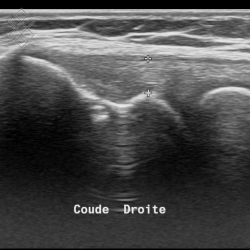

Échographie du Coude

La durée de l'examen est d'environ 20 minutes. Il est indolore et est réalisé par un médecin radiologue.